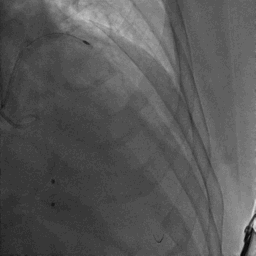

CAG:LAD近中段弥漫钙化,近段80%狭窄,中段90%狭窄,D190%狭窄,中间支近段90%狭窄,右冠近中段弥漫病变,最重狭窄50%。考虑患者胸痛症状可能为冠心病+AS共同作用,以及患者冠脉病变钙化严重,予以旋磨+PCI+TAVR一站式处理。

于中间支植入2.5*18mm支架

1.5mm旋磨头以16万RPM旋磨三次

3.0*15mm球囊后扩张

3.0*15mm球囊预处理LAD近段病变

复查冠脉造影结果满意

造影提示微少量返流,压力监测提示主动脉瓣压差7mmHg